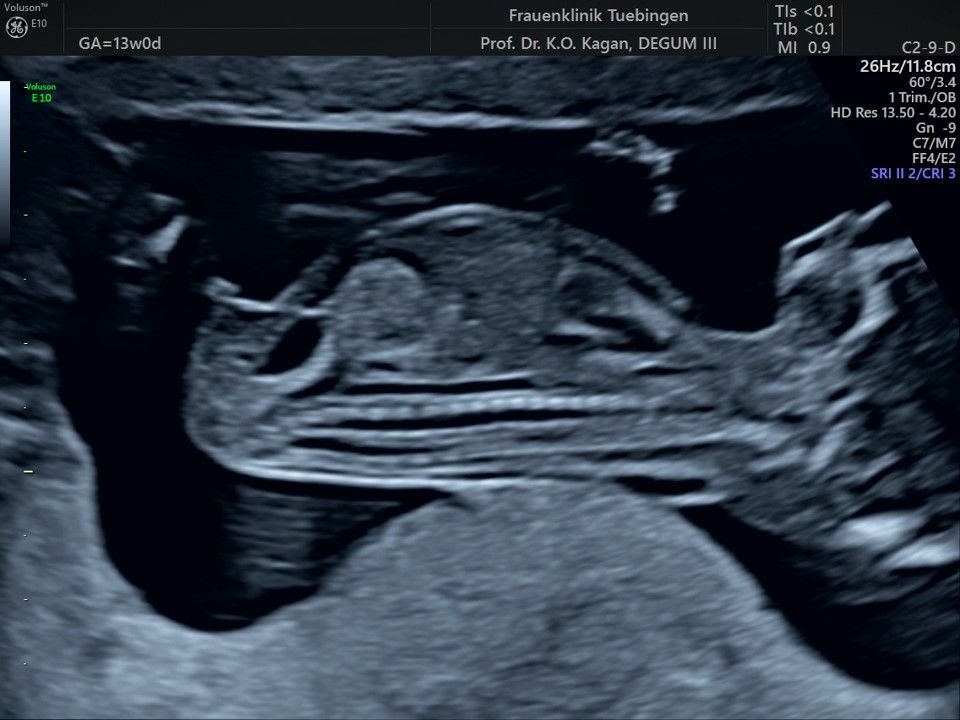

Herz

Das Ergebnis der Ultraschalluntersuchung ist wegweisend. Dabei wird der Fet vermessen, die Organe werden untersucht und die sonographischen Marker zur Risikoberechnung für Chromosomenstörungen werden beurteilt. Das sind: die Nackentransparenzdicke, Nasenbein sowie der Blutfluss in der rechten Herzhälfte und im Ductus venosus, einem Gefäß in der Leber des Feten.